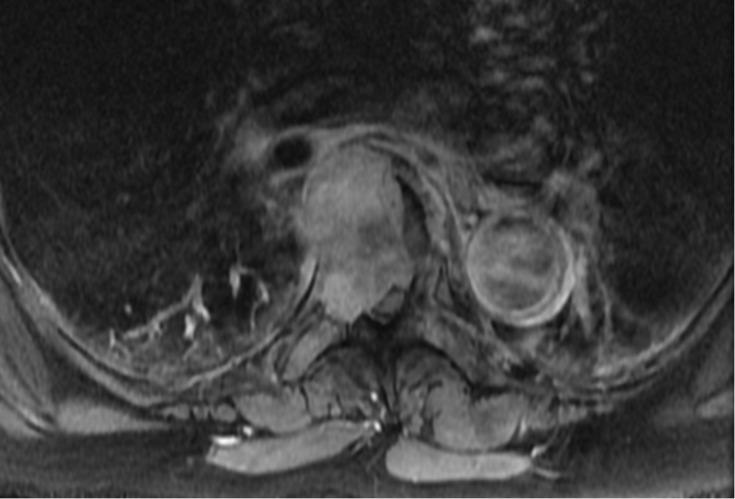

Thoracic Spinal Cord Compression Secondary to Metastatic Papillary Thyroid Carcinoma: An Unusual Oncological Phenomenon.

Cureus. 2022 Apr 17;14(4):e24206. doi: 10.7759/cureus.24206. eCollection 2022 Apr.

Unusual metastasis of papillary thyroid carcinoma to the spine: A case report.

Radiol Case Rep. 2023 Sep 7;18(11):4110-4114. doi: 10.1016/j.radcr.2023.08.078. eCollection 2023 Nov.